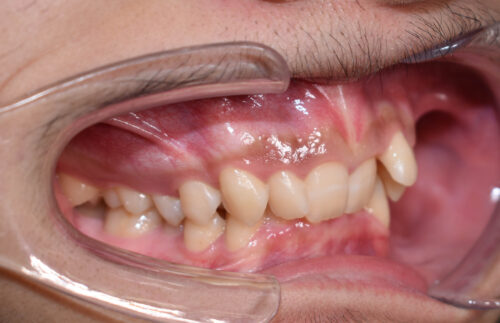

初診時年齢 17歳 男性

歯のでこぼこ (叢生)と

咬み合わせの深さ (過蓋咬合)を

気になさって

歯のがたつき(叢生)が強く認められ

また下の歯が 全く見えず 過蓋咬合の状態でした。

非抜歯矯正治療で

ワイヤー矯正治療を開始いたしました。

ワイヤー矯正治療 8か月後です。